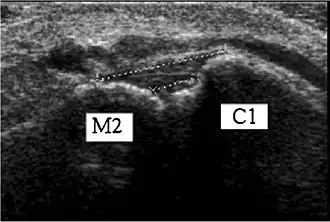

![]() Ultrasonography of the dorsal Lisfranc ligament.[1] | |

The Lisfranc ligament is one of several ligaments which connects the medial cuneiform bone to the second metatarsal. Sometimes, the term Lisfranc ligament refers specifically to the ligament that connects the superior, lateral surface of the medial cuneiform to the superior, medial surface of the base of the second metatarsal.

The Lisfranc ligament connects the medial cuneiform bone to the second metatarsal.[2] It is a complex of 3 ligaments: the dorsal Lisfranc ligament, the interosseous Lisfranc ligament, and the plantar Lisfranc ligament.[2][3]